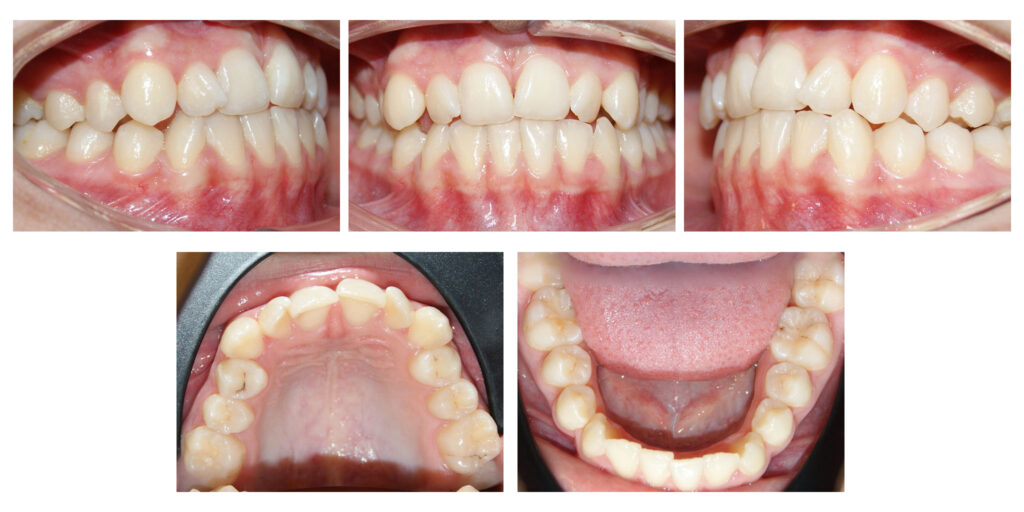

Corectarea angulațiilor dentare și a mușcăturii

Îndreptarea axelor dentare are un efect semnificativ atât asupra dinților cât și asupra țesuturilor de susținere

În cazul de față ortodonția ne-a ajutat să oferim lărgime semnificativă zâmbetului și să prevenim retracțiile gingivale de pe caninii inferiori prin distalizare.